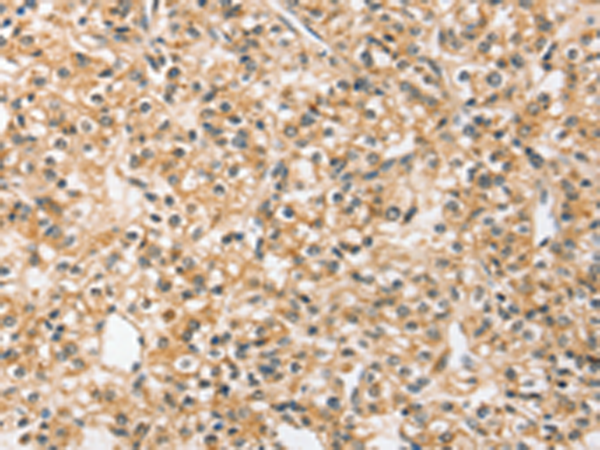

分类: 科研抗体货号: P12174别名: SIR2L4应用: IHC反应种属: Human, Mouse